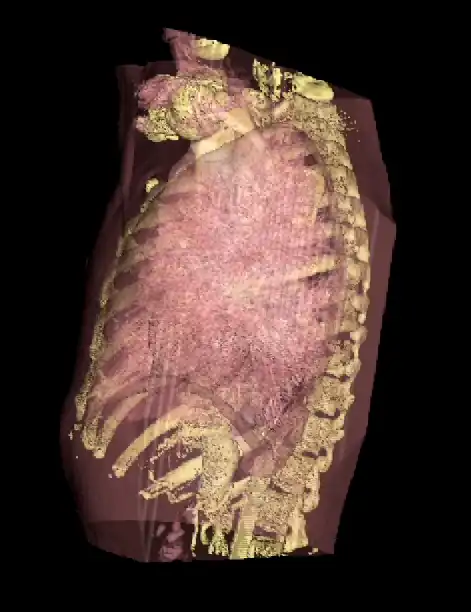

An opacity table can be applied to the results so that surfaces from internal features can also be visualized. As an example, two surfaces have been identified in the following image from the CT scan where voxel values from bone surfaces are coded in an opaque yellow colour and tissue surfaces in a transparent shade of red.